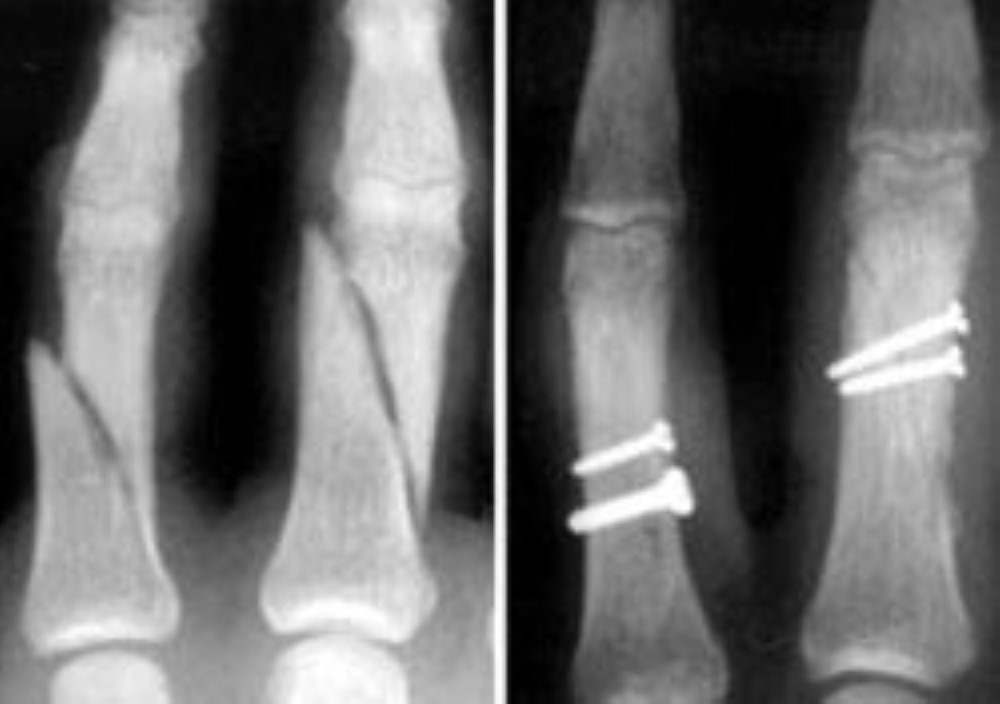

From www.johnericksonmd.com

ORIF Surgery of 4th and 5th Metacarpal Fractures John Erickson, MD Spiral Fracture Finger Healing Time It may be 3 to 4 months before full strength returns to your. If the spiral fracture is stable, treatment will usually involve keeping the bone immobilized with a cast for a period of four to six weeks. A spiral fracture is a bone fracture that occurs when a long bone is broken by a twisting force. If you think. Spiral Fracture Finger Healing Time.